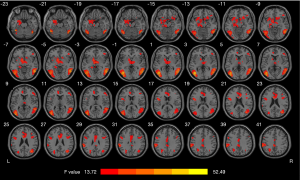

The PA, MMT, and HC groups showed significant differences in heroin cue-induced brain activation. Compared to the HCs, the MMT and PA groups demonstrated significantly higher brain activation in the left pallidum, middle occipital gyrus, postcentral gyrus, anterior cingulate cortex (ACC), middle cingulate cortex (MCC), inferior parietal lobule (IPL), superior parietal lobule (SPL), amygdala, hippocampus, right inferior temporal gyrus, inferior frontal gyrus triangularis (IFG-triang), and caudate (Figure 1, Table 4). Compared with the HCs, MMT patients showed significantly higher heroin-cue-induced brain activation in all of the regions, including the mesolimbic region (left hippocampus, cingulate cortex, and amygdala), reward-related region (right caudate and left pallidum), visuospatial-attention region (right IFG-triang, left SPL, left IPL, and left middle occipital gyrus), somatosensory cortex (left postcentral gyrus), and auditory cortex region (right inferior temporal gyrus). No difference was found in brain activation between the HC and MMT groups. MMT patients also showed significantly higher heroin-cue-induced brain activation in all of the regions mentioned above relative to the PA group. Compared with the HCs, the PA groups showed significantly higher heroin-cue-induced brain activation in the left IPL and left SPL (Figure 2).